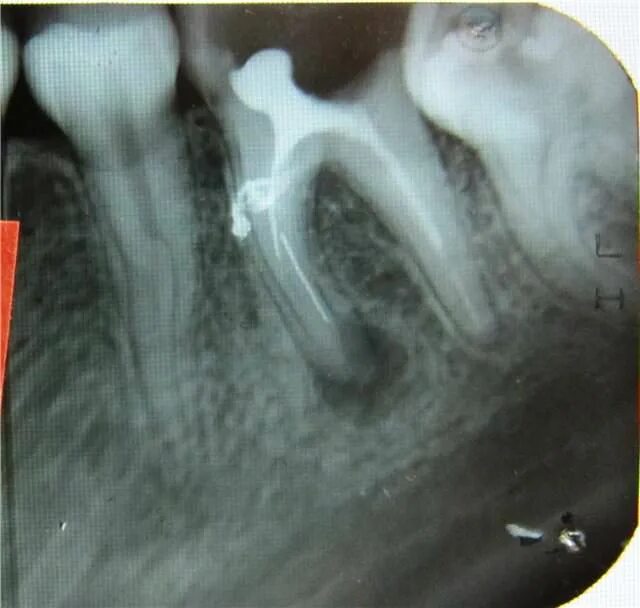

Киста зуба что это